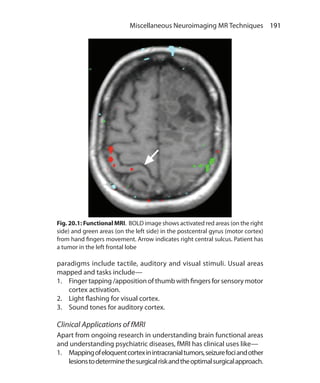

obtained

Fat and white matter are suppressed 3. CSF and water is suppressed

Mainly used in body imaging 4. Used in neuroimaging

Cannot be used in postcontrast

imaging as short T1 tissue are

suppressed and contrast shortens T1

of tissues that uptake the contrast

5. Can be used in postcontrast imaging

required to null the signal from a tissue is 0.69 times T1 relaxation

time of that tissue.

Types of IR Sequences